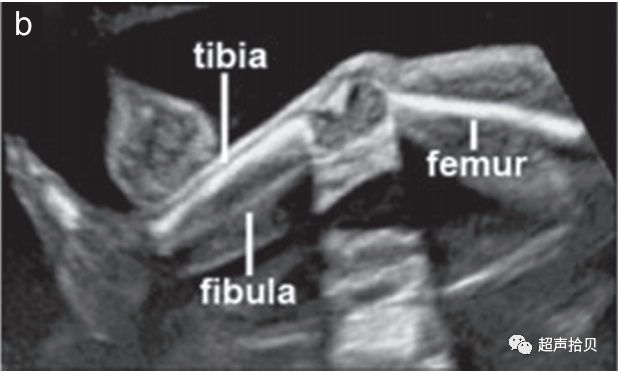

1. 手臂和手(图6a)以及腿和脚(图 6b ) 的存在与否 应使用系统方法进行观察记录;

2. 应检查所有四肢,注意所有长骨的存在及其对称性、长度、形状、对齐、位置和运动。

3. 作为孕中期常规超声检查的一部分,不需要计数手指或脚趾。

4. 通常,测量一根股骨就足够了,但如果有问题,则应测量所有长骨,并将测量值与标准化图表进行比较。

5. 标准检查中疑似偏离正常值应提示进行更详细的检查,以及可能的骨骼发育不良以及遗传和非遗传综合征的专家评估和咨询。

图6胎儿上(a)和(b)下肢的超声检查。上肢和下肢是否存在应常规观察记录,除非由于技术因素而不明显。